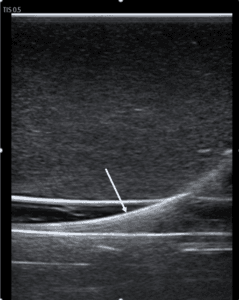

A vascular lab performed duplex ultrasound was ordered to confirm our bedside findings and revealed extensive DVT in the left lower extremity including the distal external iliac vein, CFV, proximal deep femoral vein, proximal-to-distal FV, as well as acute superficial venous thrombosis in the great saphenous vein at the level of the saphenous-femoral junction and proximal thigh (Figure 3).

Figure 3. A vascular-performed duplex ultrasound revealed acute non-compressible deep vein thrombosis in the left lower extremity involving (A) the left superficial femoral vein; (B) the left deep femoral vein; (C) the left external iliac vein; (D) the left common femoral vein.